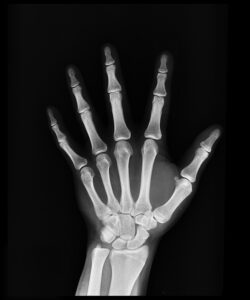

دستگاه DR یا رادیوگرافی دیجیتال، تصاویر اشعه ایکس را به صورت دیجیتال ثبت میکند و امکان مشاهده فوری، پردازش تصویر و ذخیرهسازی راحت را فراهم میکند.

3. آیا DR برای تمام نواحی بدن مناسب است؟

بله، اما برخی دستگاهها برای کاربردهای تخصصی محدودیت دارند؛ قبل از خرید یا استفاده، مطابقت دستگاه با نیاز بالینی بررسی شود.